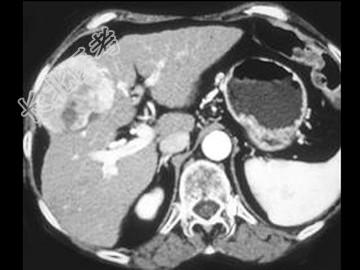

- 单项选择题女,55岁, 右上腹痛,消瘦乏力3月, 结合图像,最可能的诊断是 ( )

A、肝血管瘤

B、肝腺瘤

C、肝癌

D、肝脓肿

E、肝转移癌